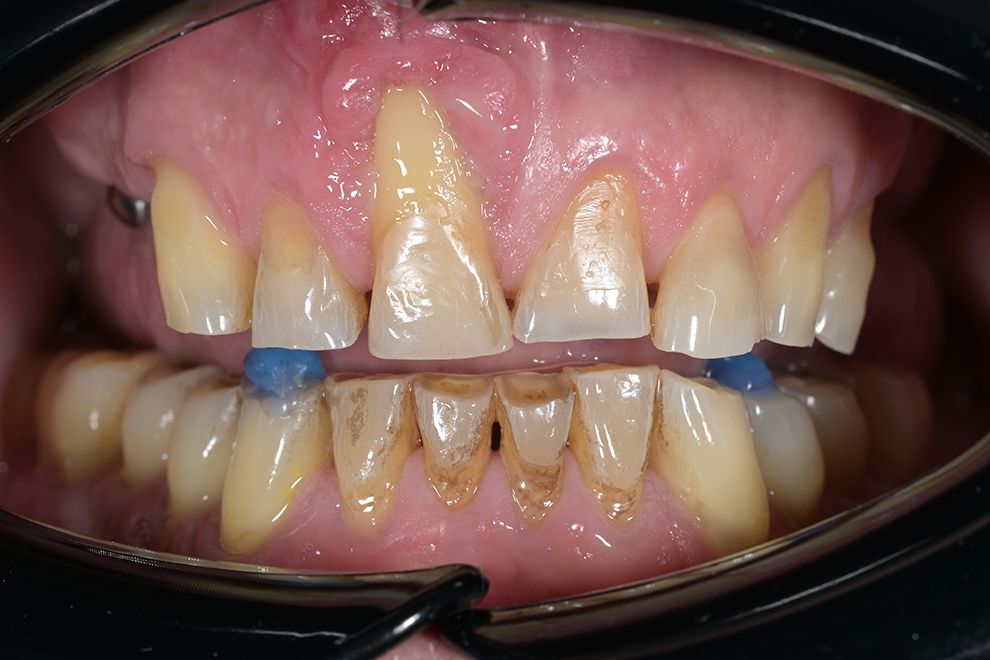

до и после